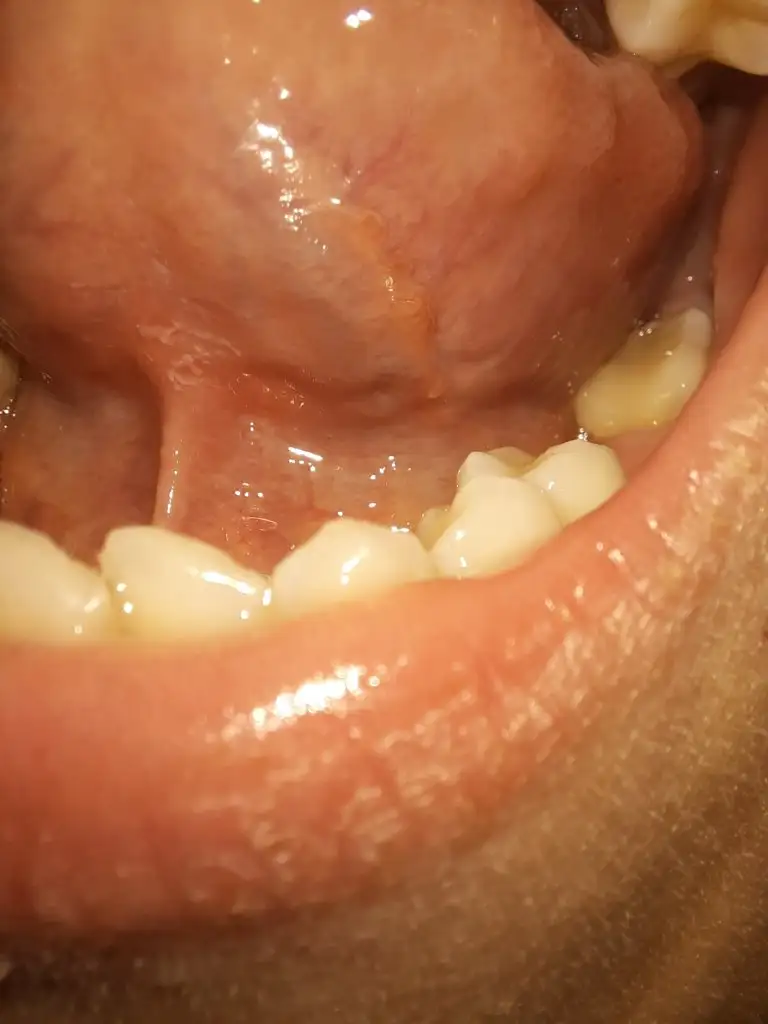

Dilimde ise bunlar var;

Böyle olan arkadaşlar var mı?

Merhaba ben kesinlikle uzman vs. Değilim ama, bu görüntüler bende de vardı, ben de telaş etmiştim ama sonra başkalarında da olduğunu gördüm. Emin olmamakla birlikte bir kişi de bunların tükürük bezi olabileceğini söyledi. Doktora özellikle sorduysanız ve sorun yok dendiyse bence rahat olun, cidden çoğu insanda var

özelde KBB ye gittim ama ilgi alanı olmadığını belirtti ve üstünkörü siğil dedi.

Bir doktora gitmekte daha fayda var ama dediğim gibi bu yapıları 1-2 kişi hariç çevremdeki çoğu insanda özellikle gördüm. Bi sıkıntı yokmuş gibi hissediyorum ama siz yine de bir doktora daha gidin bence💐

Benim dil yapımda böyle bence siğille alakası yok canım ya siğil olsa ağzın başka kısımlarında da çıkar ve genelde boğazda çıkıyor diyorlar ama için rahat etsin sen yine git ama ben hiç takmadım açıkcası siğil olduğunu düşünmüyorum